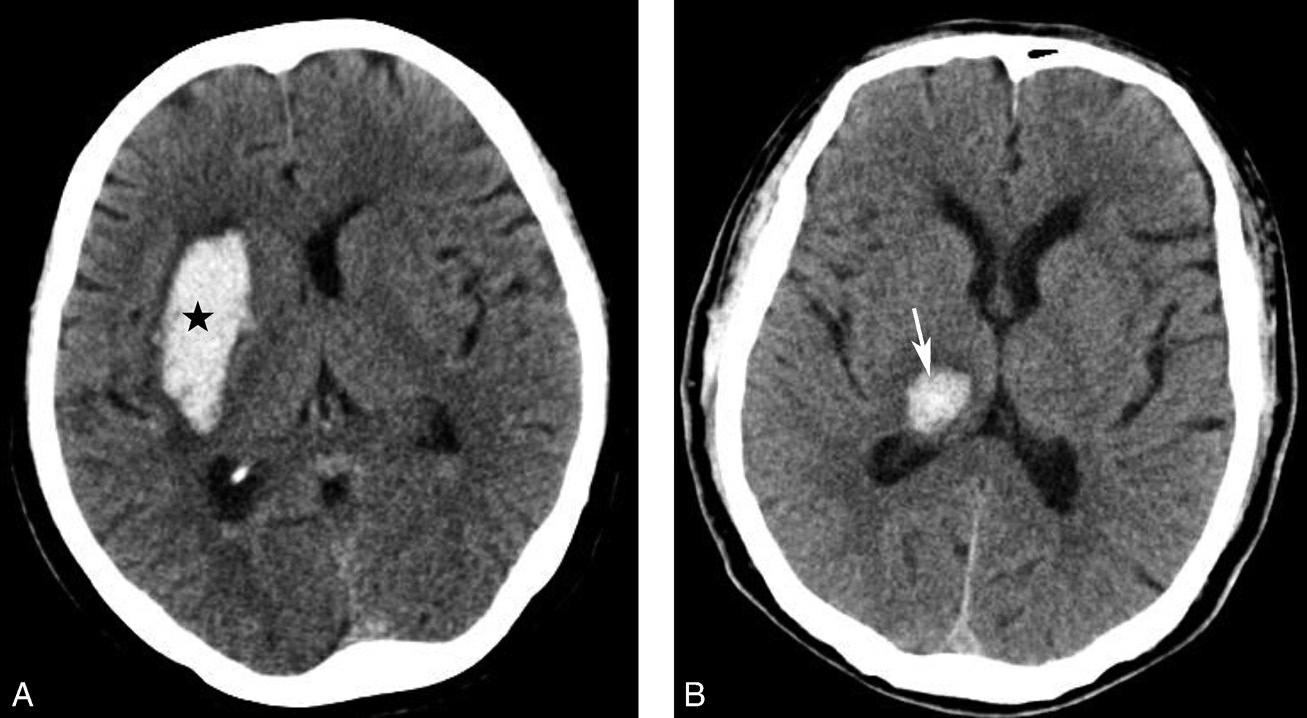

图1-2-32 脑出血

A.右侧壳核脑出血,形成高密度血肿(★);B.右侧丘脑出血,呈球形高密度影(箭)

图1-2-33 基底节区脑梗死

A.右侧丘脑梗死,病灶呈圆形低密度影(箭);B.左侧内囊膝部及后肢梗死,呈带状低密度影(箭)